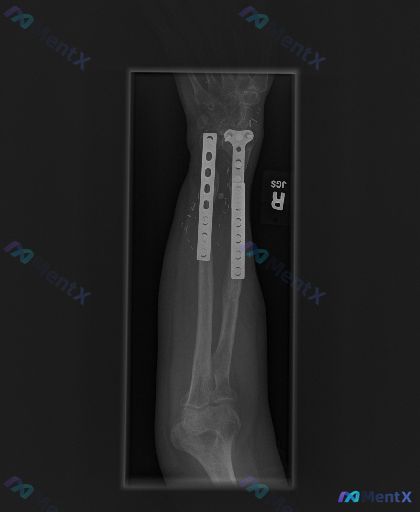

各位骨科同道,今天分享一个右前臂远端双骨折内固定术后的复查病例,一起探讨影像表现的临床意义。 病例资料 患者为右前臂远端桡骨、尺骨双骨折切开复位内固定术后,目前为术后复查阶段。 影像表现摘要 1. 内固定情况:桡骨远端见解剖锁定钢板,尺骨远端见直型接骨板,多枚螺钉固定,内固定物位置稳固,未见明显断钉...